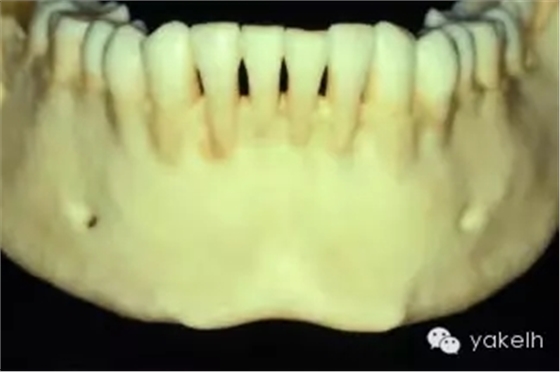

¤¤許多上頜竇以及Onlay植骨的移植物來自于下頜骨頦部。已有報(bào)道從下頜骨前牙區(qū)獲取塊狀骨以及顆粒狀骨的技術(shù)。頦部是口內(nèi)能提供最大骨量的區(qū)域(圖13.15)。兩頦孔間的平均距離為5cm,平均厚度為1cm。CT掃描以及全景片能夠評(píng)估該區(qū)的可供骨量。頭影測(cè)量片可測(cè)定下頜骨前牙區(qū)的前后徑。根尖片能更精確地測(cè)量牙根長(zhǎng)度。

圖13.15 干燥的標(biāo)本提示,從下頜骨頦部可以獲取大量的骨質(zhì)。